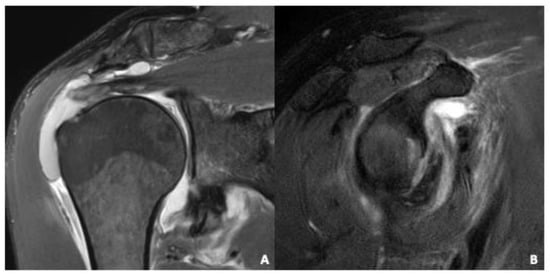

| Bone | Assessment for osseous defects such as osseous/bony Bankart and Hill-Sachs lesions [28] | Normal signal: 1 (63%) Greater tuberosity fracture: 2 (5%) Hill Sachs defect: 29 (88%), Osseous/Bony Bankart defect: 14 (42%) |

| Labrum | Assessment for defects of the labrum e.g., antero- inferior after dislocation, anatomical variations of the labrum according to Kanatli et al. [29] | Normal Labrum: 1 (3%) Anatomical normal variant: 0 (3%) Lesion: 32 (97%) |

| Cartilage | Visual grading of signal inhomogeneities or defects of articular cartilage | Normal signal: 25 (76%) Abnormal: 8 (24%) |